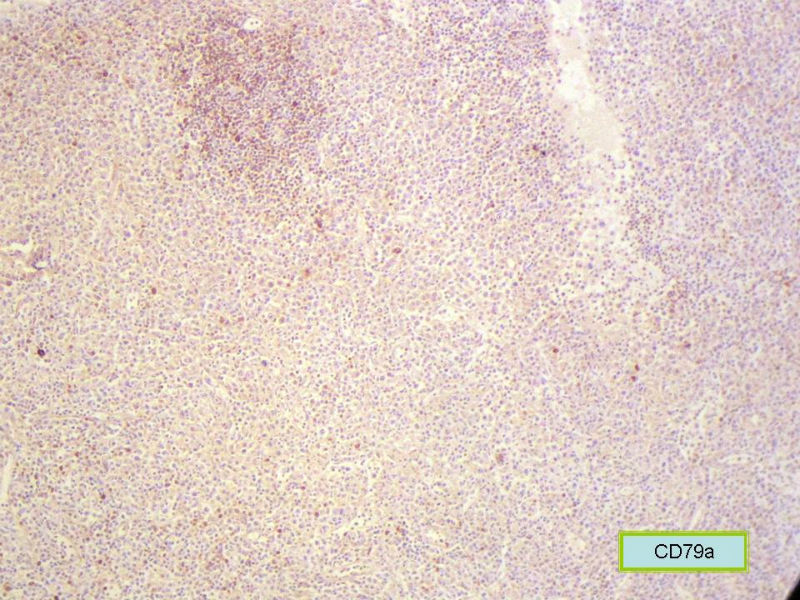

该患者可能存在病毒的感染,抑或是EB病毒的感染,包括CD30+的细胞在内,夹杂在组织细胞、小淋巴细胞之间的一些个大细胞是活化的淋巴细胞,表型看来属B细胞。整个形态呈反应性增生的形态。

总之,现有的图片显示的形态和IHC标记尚不足以诊断为淋巴瘤,除非有有基因重排的支持。